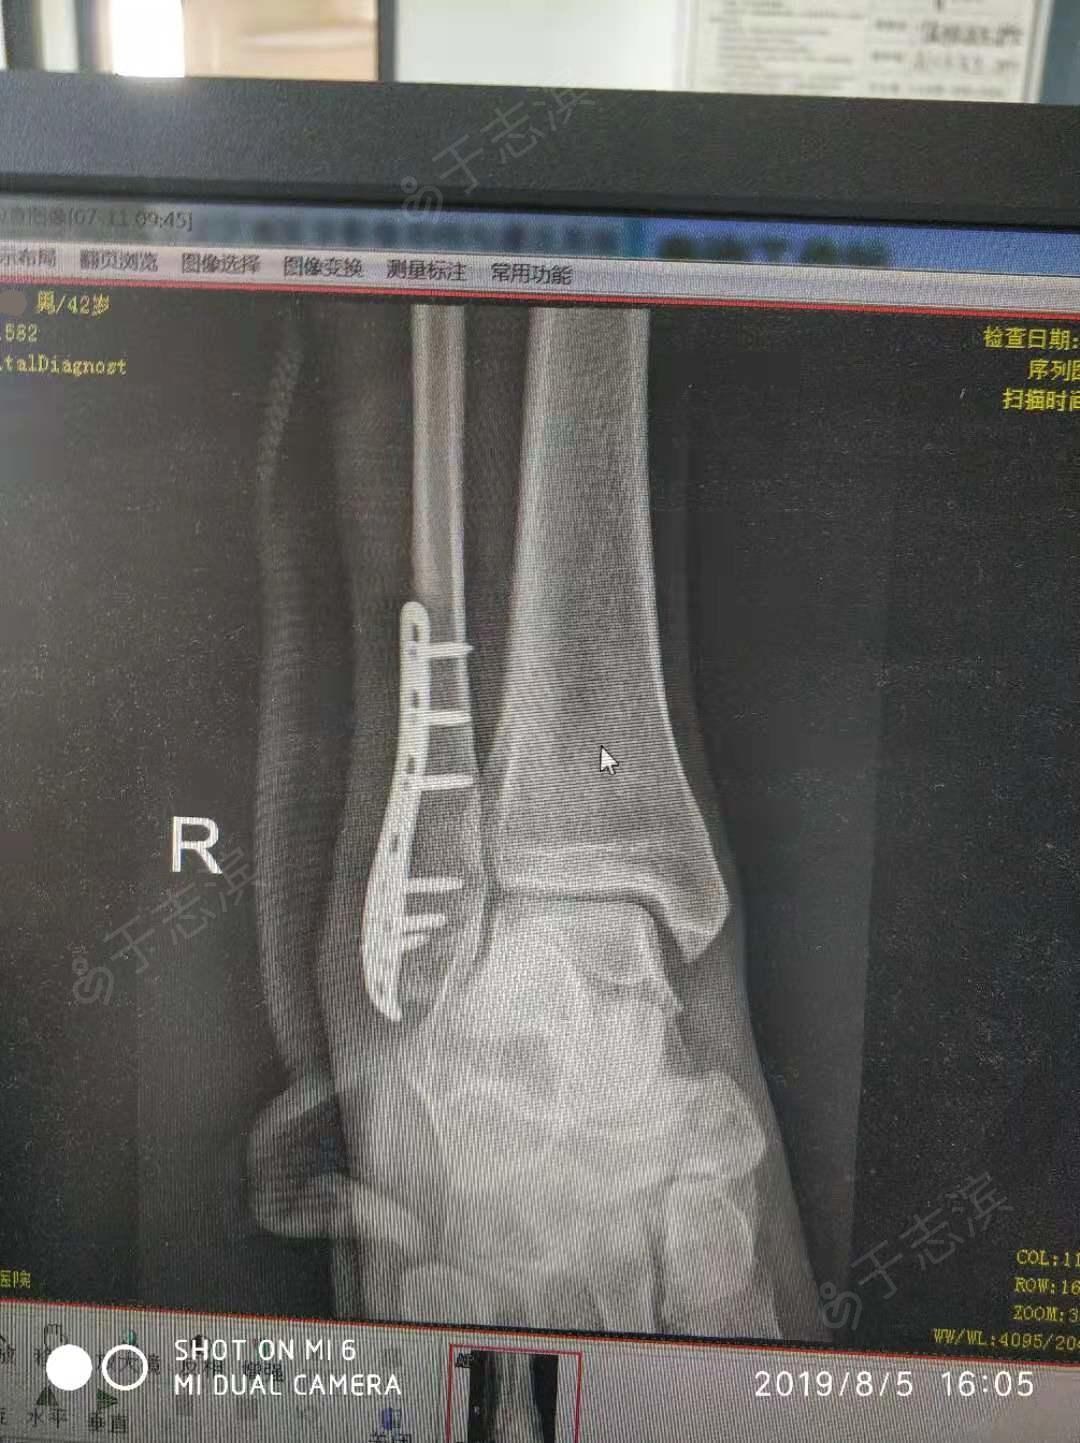

右外踝骨折切开复位内固定术

首页 / 腓骨外踝骨折 / 图片详情